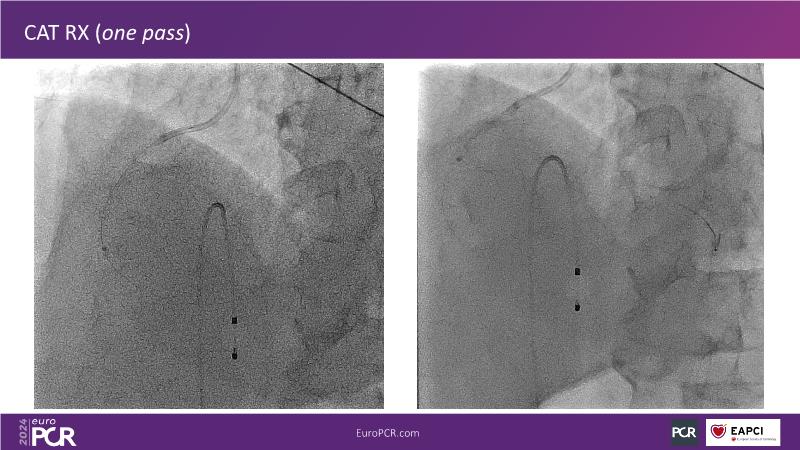

Tune into this 2024 session for insights into the latest ESC guidelines, strategies to prevent and treat no reflow, and an examination of trials like TASTE, TAPAS, and TOTAL on coronary thrombus management. Explore also the outcomes of the CHEETAH study, pondering a potential paradigm shift, and delve into a case study on thrombus removal in a patient with high thrombus burden.